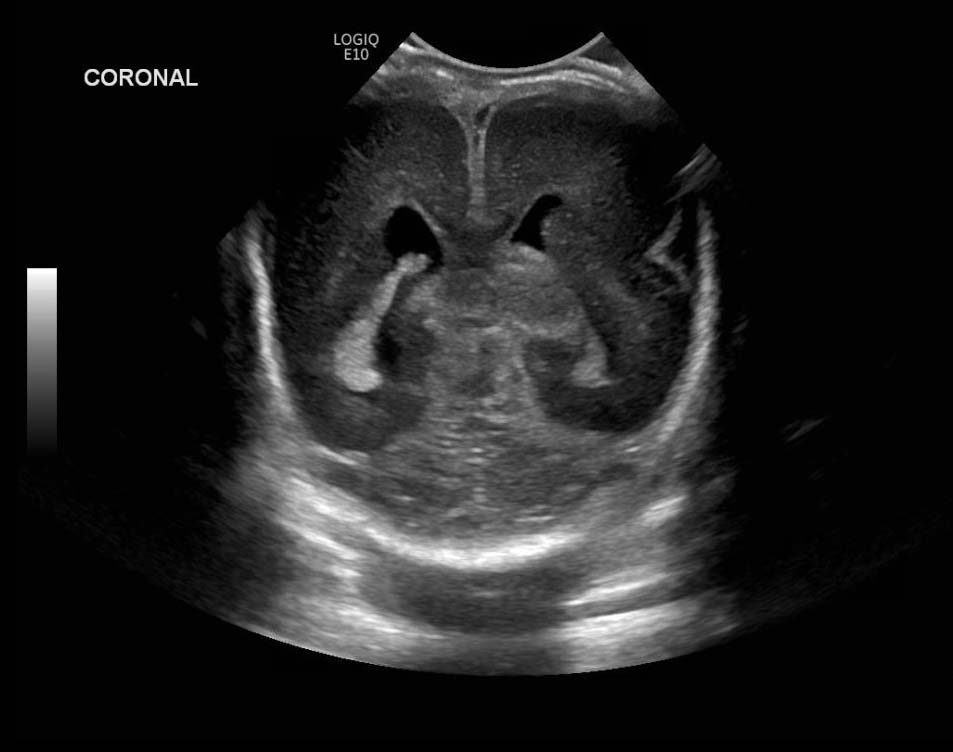

Age: 4 days (born at 24 weeks)

Sex: Male

Indication: Evaluate for germinal matrix hemorrhage

Grade 2 germinal matrix hemorrhage

Sample ReportLeft germinal matrix hemorrhage involving the caudothalamic groove and layering in the occipital horn of the left lateral ventricle without hydrocephalus (grade 2).

No abnormal brain parenchymal echogenicity or extra-axial collections.

Premature sulcation pattern.